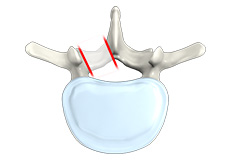

Foraminoplasty

Neural foramina are small canals at every level of the spine through which nerves leave the spinal cord and go to the limbs and other parts of the body. Narrowing of this canal is called foramina stenosis. The narrowing may be caused by bone spurs, a herniated or bulging disc, arthritis, ligament thickening or enlargement of a joint in the spinal canal.